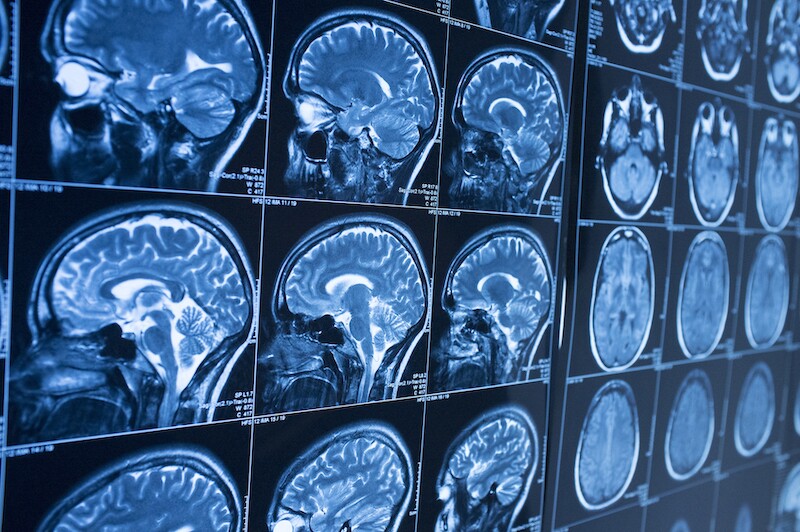

Imaging techniques are currently unable to diagnose CTE in living patients. To diagnose CTE, doctors need to dissect and weigh the brain. As a result, doctors can only diagnose CTE after death.

When examining the brain of a patient with advanced CTE, doctors will see visible shrinkage of the brain. They can also find gaps in the brain tissue where the brain has atrophied. Finally, the brain of a CTE patient often weighs significantly less than a healthy brain.